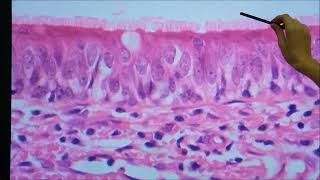

pra ver que no vídeo mas quando vocês ou manusearem a peça no laboratório e se vai ficar mais claro então vamos começar a parte mais interna para mais externa é inicialmente primeiro é aqui a gente tem um epitélio que é estratificado à noite várias camadas e pavimenta e pavimentou zhu e que era utilizado essa característica de qualquer parte da pele sempre eterno estratificado com várias camadas a camada de cima vai ser com células achatadas por isso o pavimento ozu e uma camada córnea ou de queratina que evita nem a perda de água a camada mais

profunda que vai estar em contato com a lâmina ou membrana basal a gente chama de camada basal nessa camada basal aquilo predominar células tronco que são células que vão dar origem às outras células que vão se diferenciando aqui lembra que a gente vai perdendo as celas por descamação todos os dias em nossas celas são respostas por essas células tronco que fica aqui bem para mas o tecido conjuntivo que a fonte de nutrientes na que terry não tem da escolarização normalmente essas células são cilíndricas a gente vai ver depois na lâmina acima dessa camada basal é

uma única camada de células tarso cilíndricas a gente vai ter uma camada mais espessa e é representado pela letra d essa parte amarela daqui que a gente chama de camada ou extrato é espinhoso esse nome espinhoso é porque as células quando a gente observar no microscópio elas possuem várias vários desmandos somos que são um tipo de junção intercelular esses desmandos sons quando a gente prepara lâmina e utilizo ao com as células retraem e nunca cela retrai perda de água o desembolso uma permanece como se fossem pequenos espinhos entre uma célula e outra por isso que

uma espinhosa e os 10 nós somos importantes para dar maior adesão e firmeza à pele então a gente tem camada basal chamada espinhosa a iac na letra você vai ter uma camada fina que vai achar acho ser chamada de camada granulosa nome granulosa porque as células apresentar vários grammys que são os precursores da queratina ou camada córnea quem chama de grânulos de que era ato e alina por isso o nome granulosa que representado pela letra c e no caso aqui da pele fina a camada mais as logo acima dessa gente que a camada córnea ou

camada de queratina que essas células que vão morrendo por apoptose e vão sendo liberados restos de células e esse argumento de queratina então essa característica geral aqui dá da epiderme isso na pele fina na pele espessa a gente vai ter as mesmas camadas uma camada mais sob a camada basal que é igual a camada espinhosa camada um extrato da mesma coisa espinhosa extrato granuloso e nesse caso aparece uma nova camada que é bem sutil um pouco mais difícil de visualizar na lâmina que a gente chama de citrato lúcido que é a na região onde as